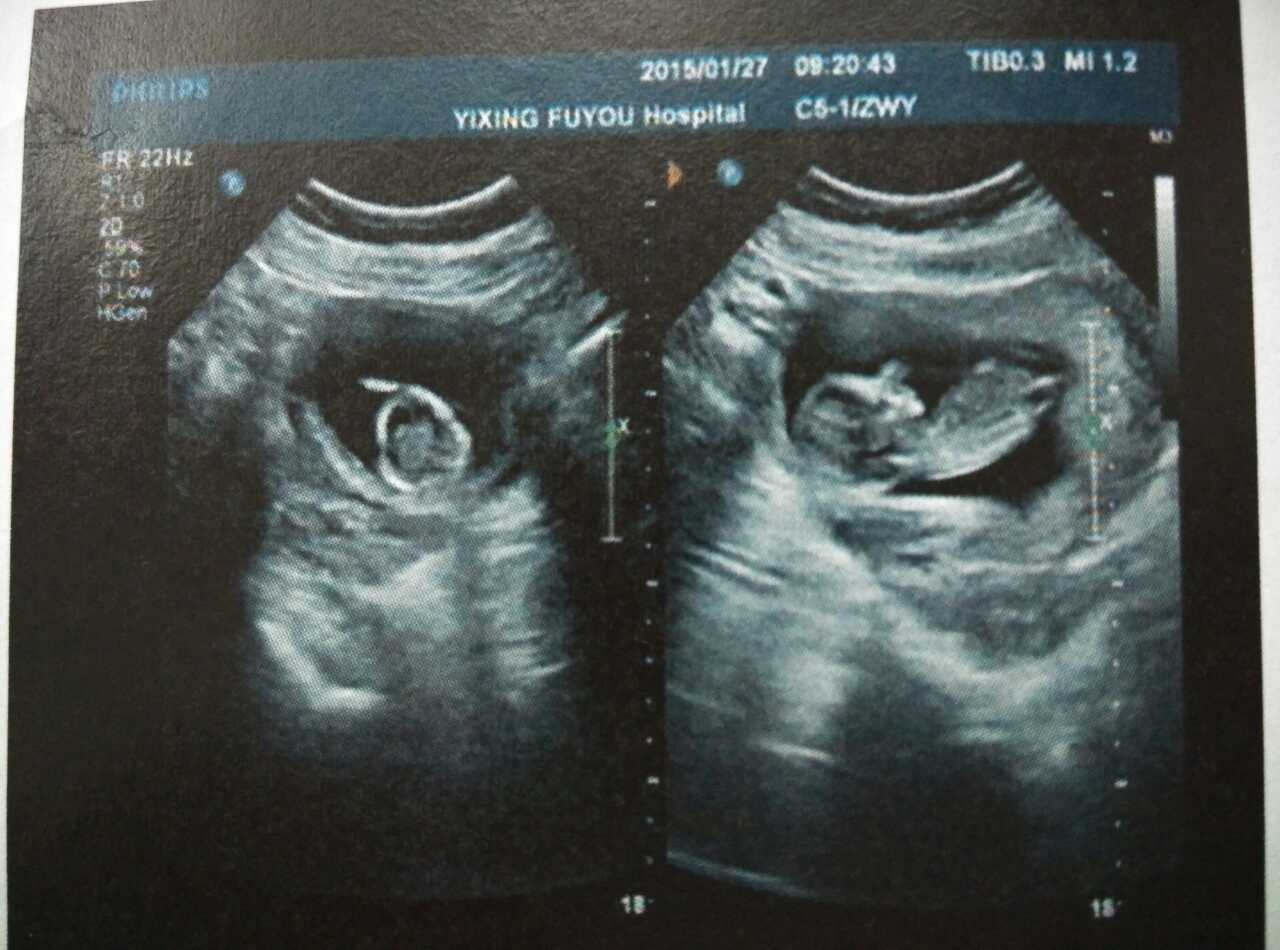

其实从胎儿孕育到宝宝出生的十个月内,宝宝在妈妈的肚子里面,每个月都会有不同的变化,看了这些变化,我们不禁感叹,这就是生命,这就是我们在妈妈肚子中的生活!

2、 怀孕初期:2个月

两个月左右的时候,已经能够看到胎儿的雏形,妈妈的子宫壁也变得越来越薄。